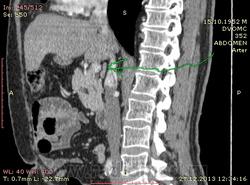

61 год. Рак желудка, в 2011 году субтотальная резекция. Жалоб нет. На вид здоровый, не худой, розоволицый мужик. На УЗИ нашли гиперэхогенное образование в VI сегменте печени 0.8 х 0.6 см. Рекомендовали КТ. Ну и вот: в печени в VI сегменте мелкий кальцинат...больше ничего страшного не вижу. В аорте куча мягких и "твердых" бляшек. Очень интересует Ваше мнение по поводу найденых, как мне кажется, достаточно крупных лимфоузлов...не похожи на метастатическое поражение?

Желудок резецирован по Б-II, лимфоузлы не увеличены. Подпеченочный аппендикс.

и в портальную фазу практически равны по плотности сосудам. Нормальные лимфоузлы всегда гиподенснее сосудов. Форма лимфоузлов может быть любой, и лишь округлость во всех реконструкциях может свидетельствовать о лимфаденопатии. Обычно паракавальный узел крупный и овально-округлый в короналах, но уплощенный на сагитталах, как в вашем случае - нормальный. Не всегда видны жировые ворота лимфоузла. При воспалительной лимфаденопатии узел может быть крупным, "набухшим", при сохранении жировых ворот. Округлый лимфоузел размерами даже меньше нормы в коротком поперечнике, но с патологическим накоплением контраста, считается измененным, и подозрителен на метастаз.

Для информации: симуляция паракавальной лимфаденопатии: